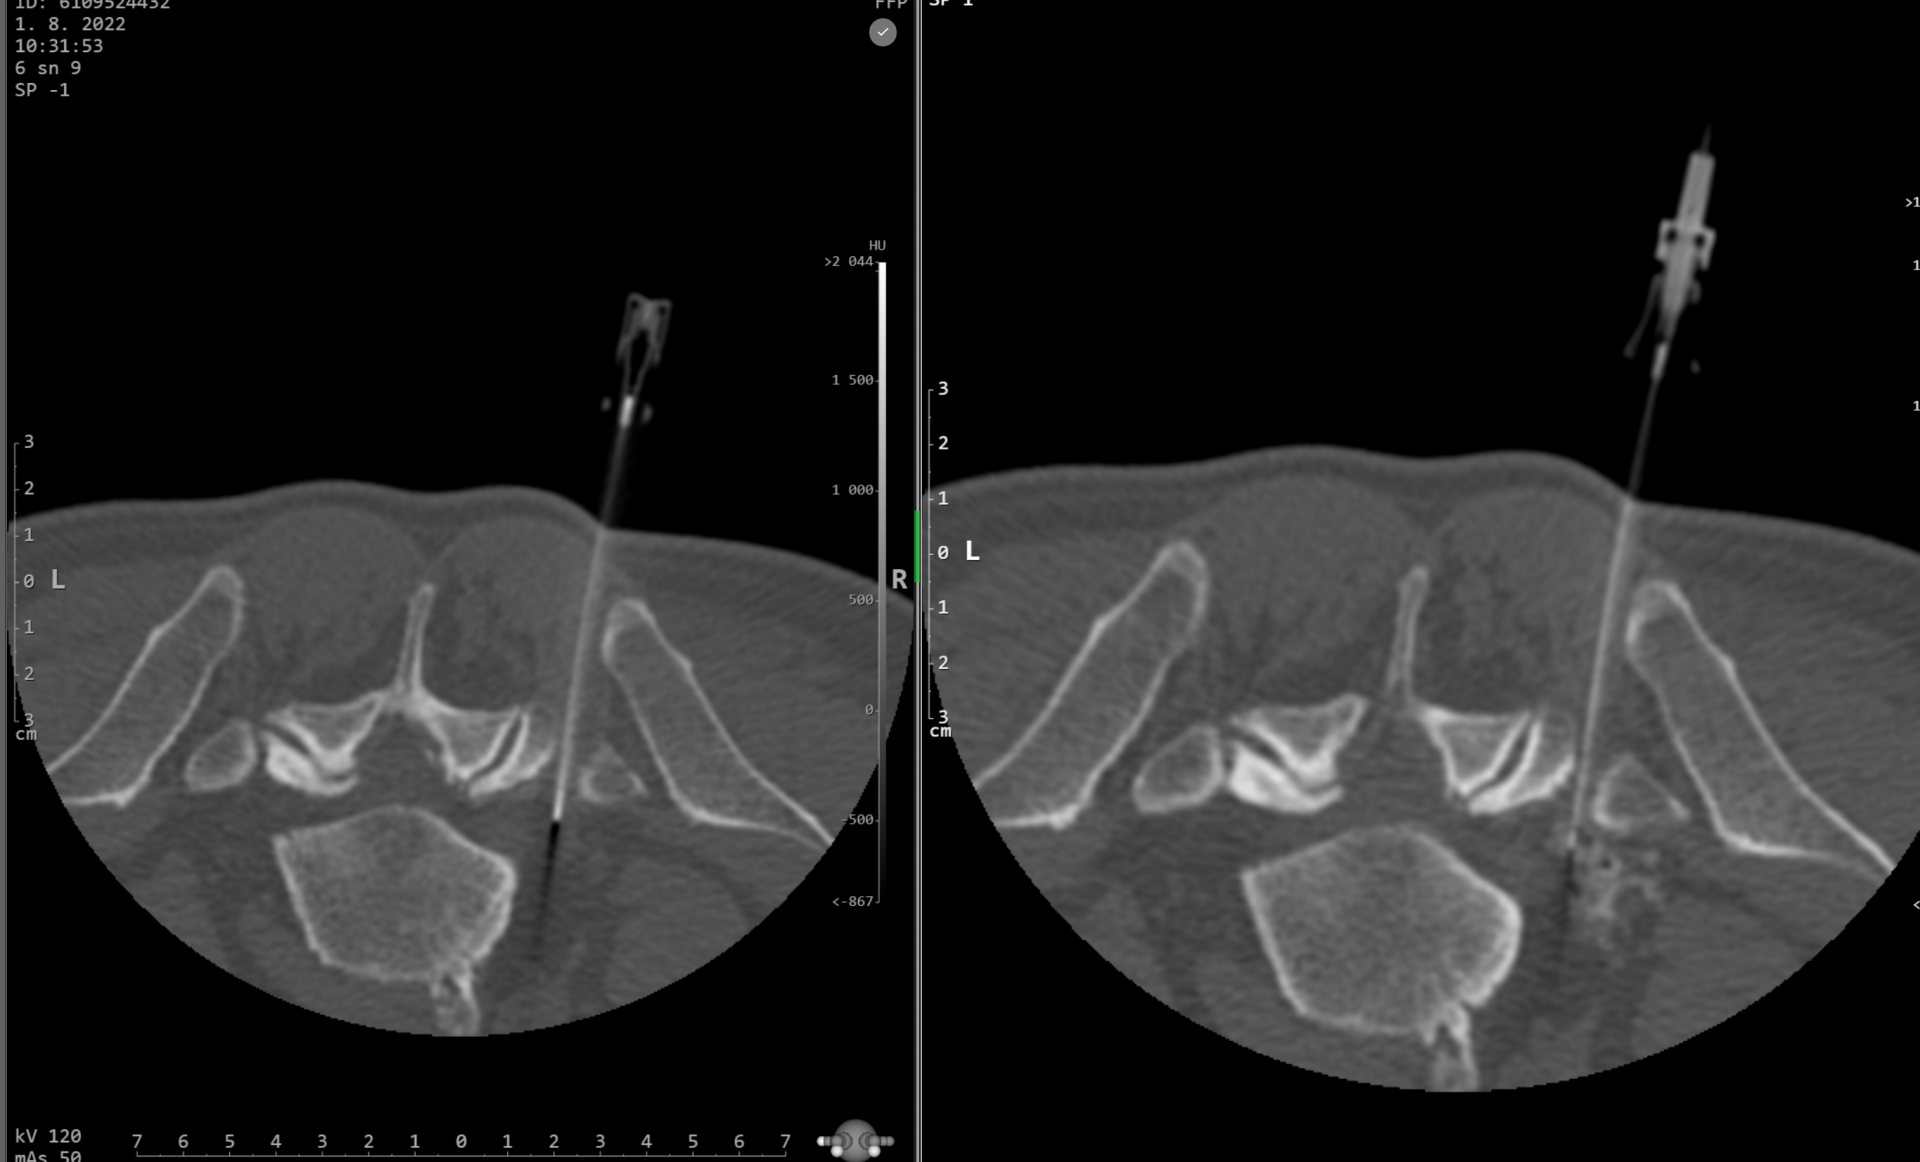

Obstřik kloubků páteře – facetová denervace (FD) a obstřik SI (křížokyčelního) skloubení

Tento zákrok je vhodný pro pacienty s bolestmi zad a křížové oblasti při degenerativních změnách (artróze) drobných kloubů páteře a SI sloubení.

Průběh výkonu

Výkon je obvykle rychlý a minimálně bolestivý.

Pacient při výkonu leží na břiše. Úvodem se provede vyšetření vybraného úseku páteře k přesnému zacílení výkonu. Po výběru místa vhodnému k vpichu je kůže zad natřena desinfekcí.

Poté je k meziobratlovému/SI kloubu zavedena velmi tenká jehla. Po přesném umístění hrotu jehly je ke kloubu aplikována směs 3,5 ml Marcainu a 1 ml Diprophosu.

Marcain je dlouhodobě působící lokální anestetikum. Diprophos kortikoid má protizánětlivé a antiedematozní účinky.